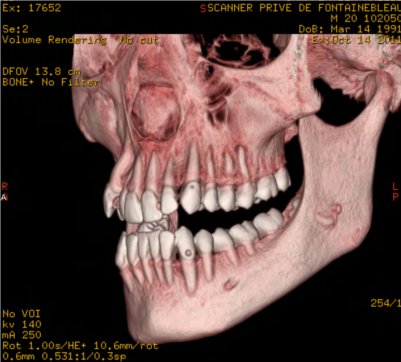

Les nouvelles générations de scanner permettent de faire une acquisition d’un volume global d’une partie du corps et de travailler à l’intérieur de ce volume en isolant une structure anatomique donnée et de l’explorer dans tous les plans de l’espace.

Grace à la technique de seuillage il est possible de dissocier progressivement les dents des structures osseuses environnantes dans le volume donné.